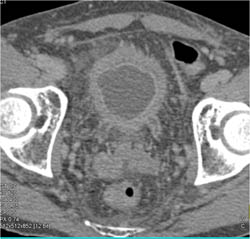

Pancreatic Transplant With CT Cystogram Showing Anastomosis